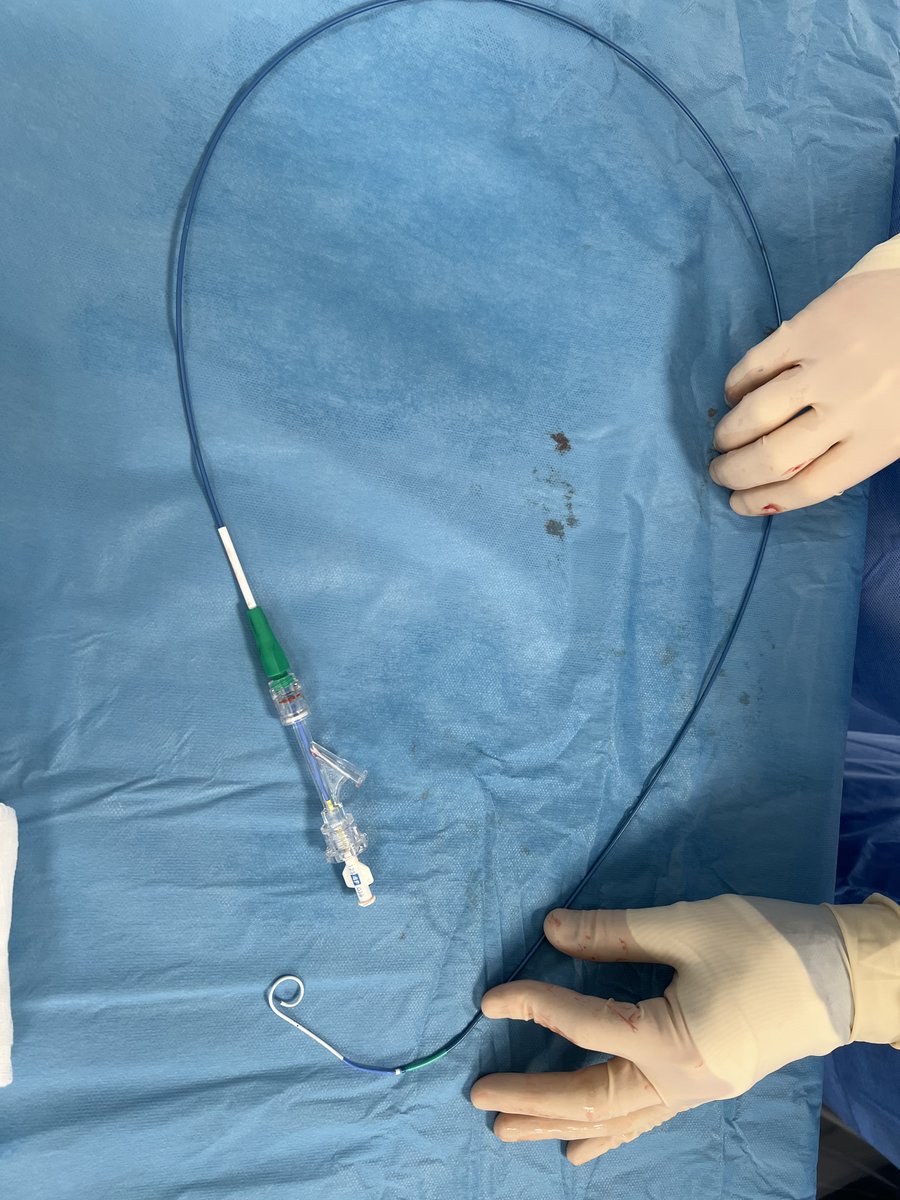

Use a 5 Fr Halo One thin-walled hydrophilic sheath with a 4 Fr pigtail. Or in this case a 6 Fr Halo One thin-walled hydrophilic sheath with a 5 Fr Jacky (just for pressure measurement, no LV grams with end hole catheters!) Sheath tip in central Ao. #CathLabHacks #CardioTwitter